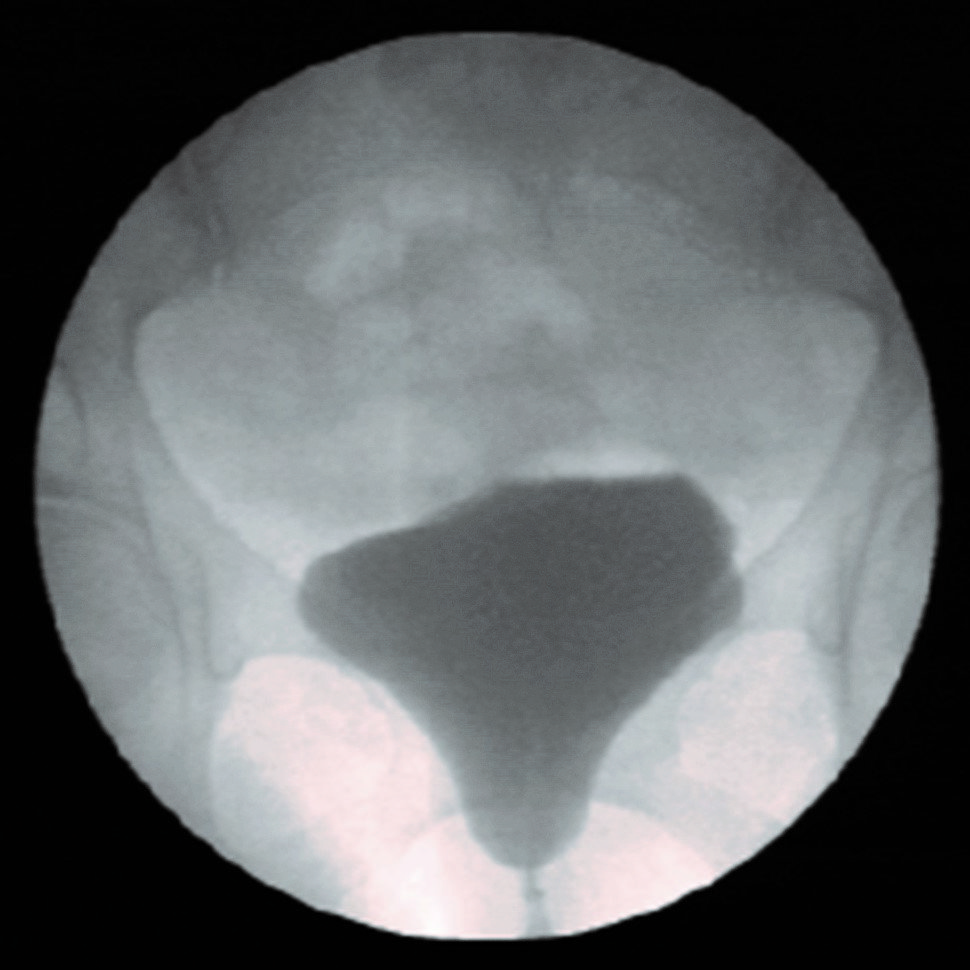

- Video-Urodynamik

Video-Urodynamik

- Verarbeitung von hochauflösenden, analogen und digitalen Eingangssignalen

- Digitale Echtzeitaufnahme und

-sequenzen - DICOM Dokumentation